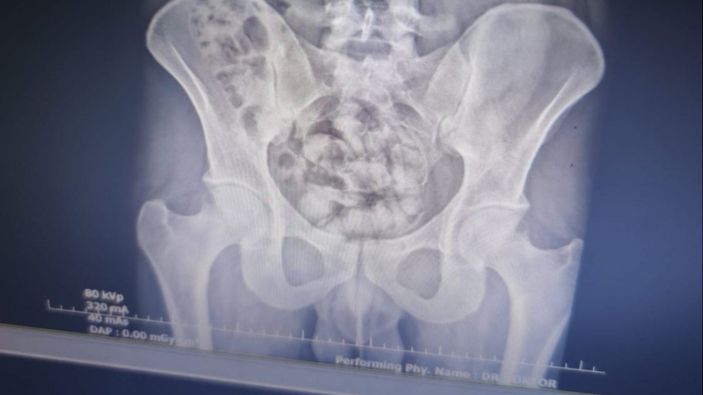

MİDESİNDE 25 KAPSÜL BULUNDU

Burada çekilen röntgen filminde, midesinde 25 kapsül şeklinde paketlenmiş halde 351 gr gelen metamfetamin olduğu tespit edildi.

Hayatını riske atarak kuryelik yaptığı saptanan S.Y., midesindeki kapsül halindeki uyuşturucunun doğal çıkması için gözlem altına alındı.